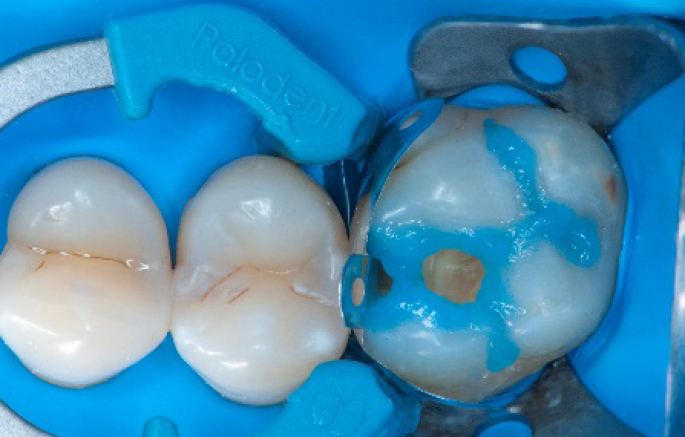

Step 8:

Transformation of class II into class I, restoring the interproximal wall with Spectra ST4 composite in shade A2.

Step 9:

Transformation of a big class I into a small class I, using SDR® flow+ material in one increment up to 4 mm.

Step 10:

The situation after the application of SDR® flow+ material.